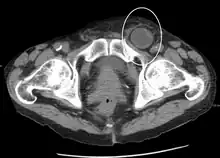

In the diagnosis of abdominal hernias, imaging is the principal means of detecting internal diaphragmatic and other nonpalpable or unsuspected hernias. Multidetector CT (MDCT) can show with precision the anatomic site of the hernia sac, the contents of the sac, and any complications. MDCT also offers clear detail of the abdominal wall allowing wall hernias to be identified accurately.[9]